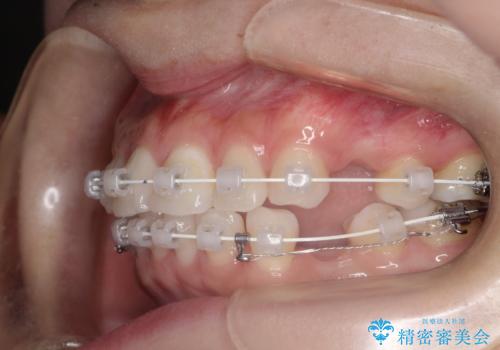

口が閉じにくい 口ゴボの抜歯矯正による改善

- 審美装置

- 2年1ヶ月

- 口が閉じずらく、口元が出ていることを主訴に来院されました。

上下左右の歯を1本ずつ抜歯して、そのスペースを利用して口元を引っ込める計画としました。